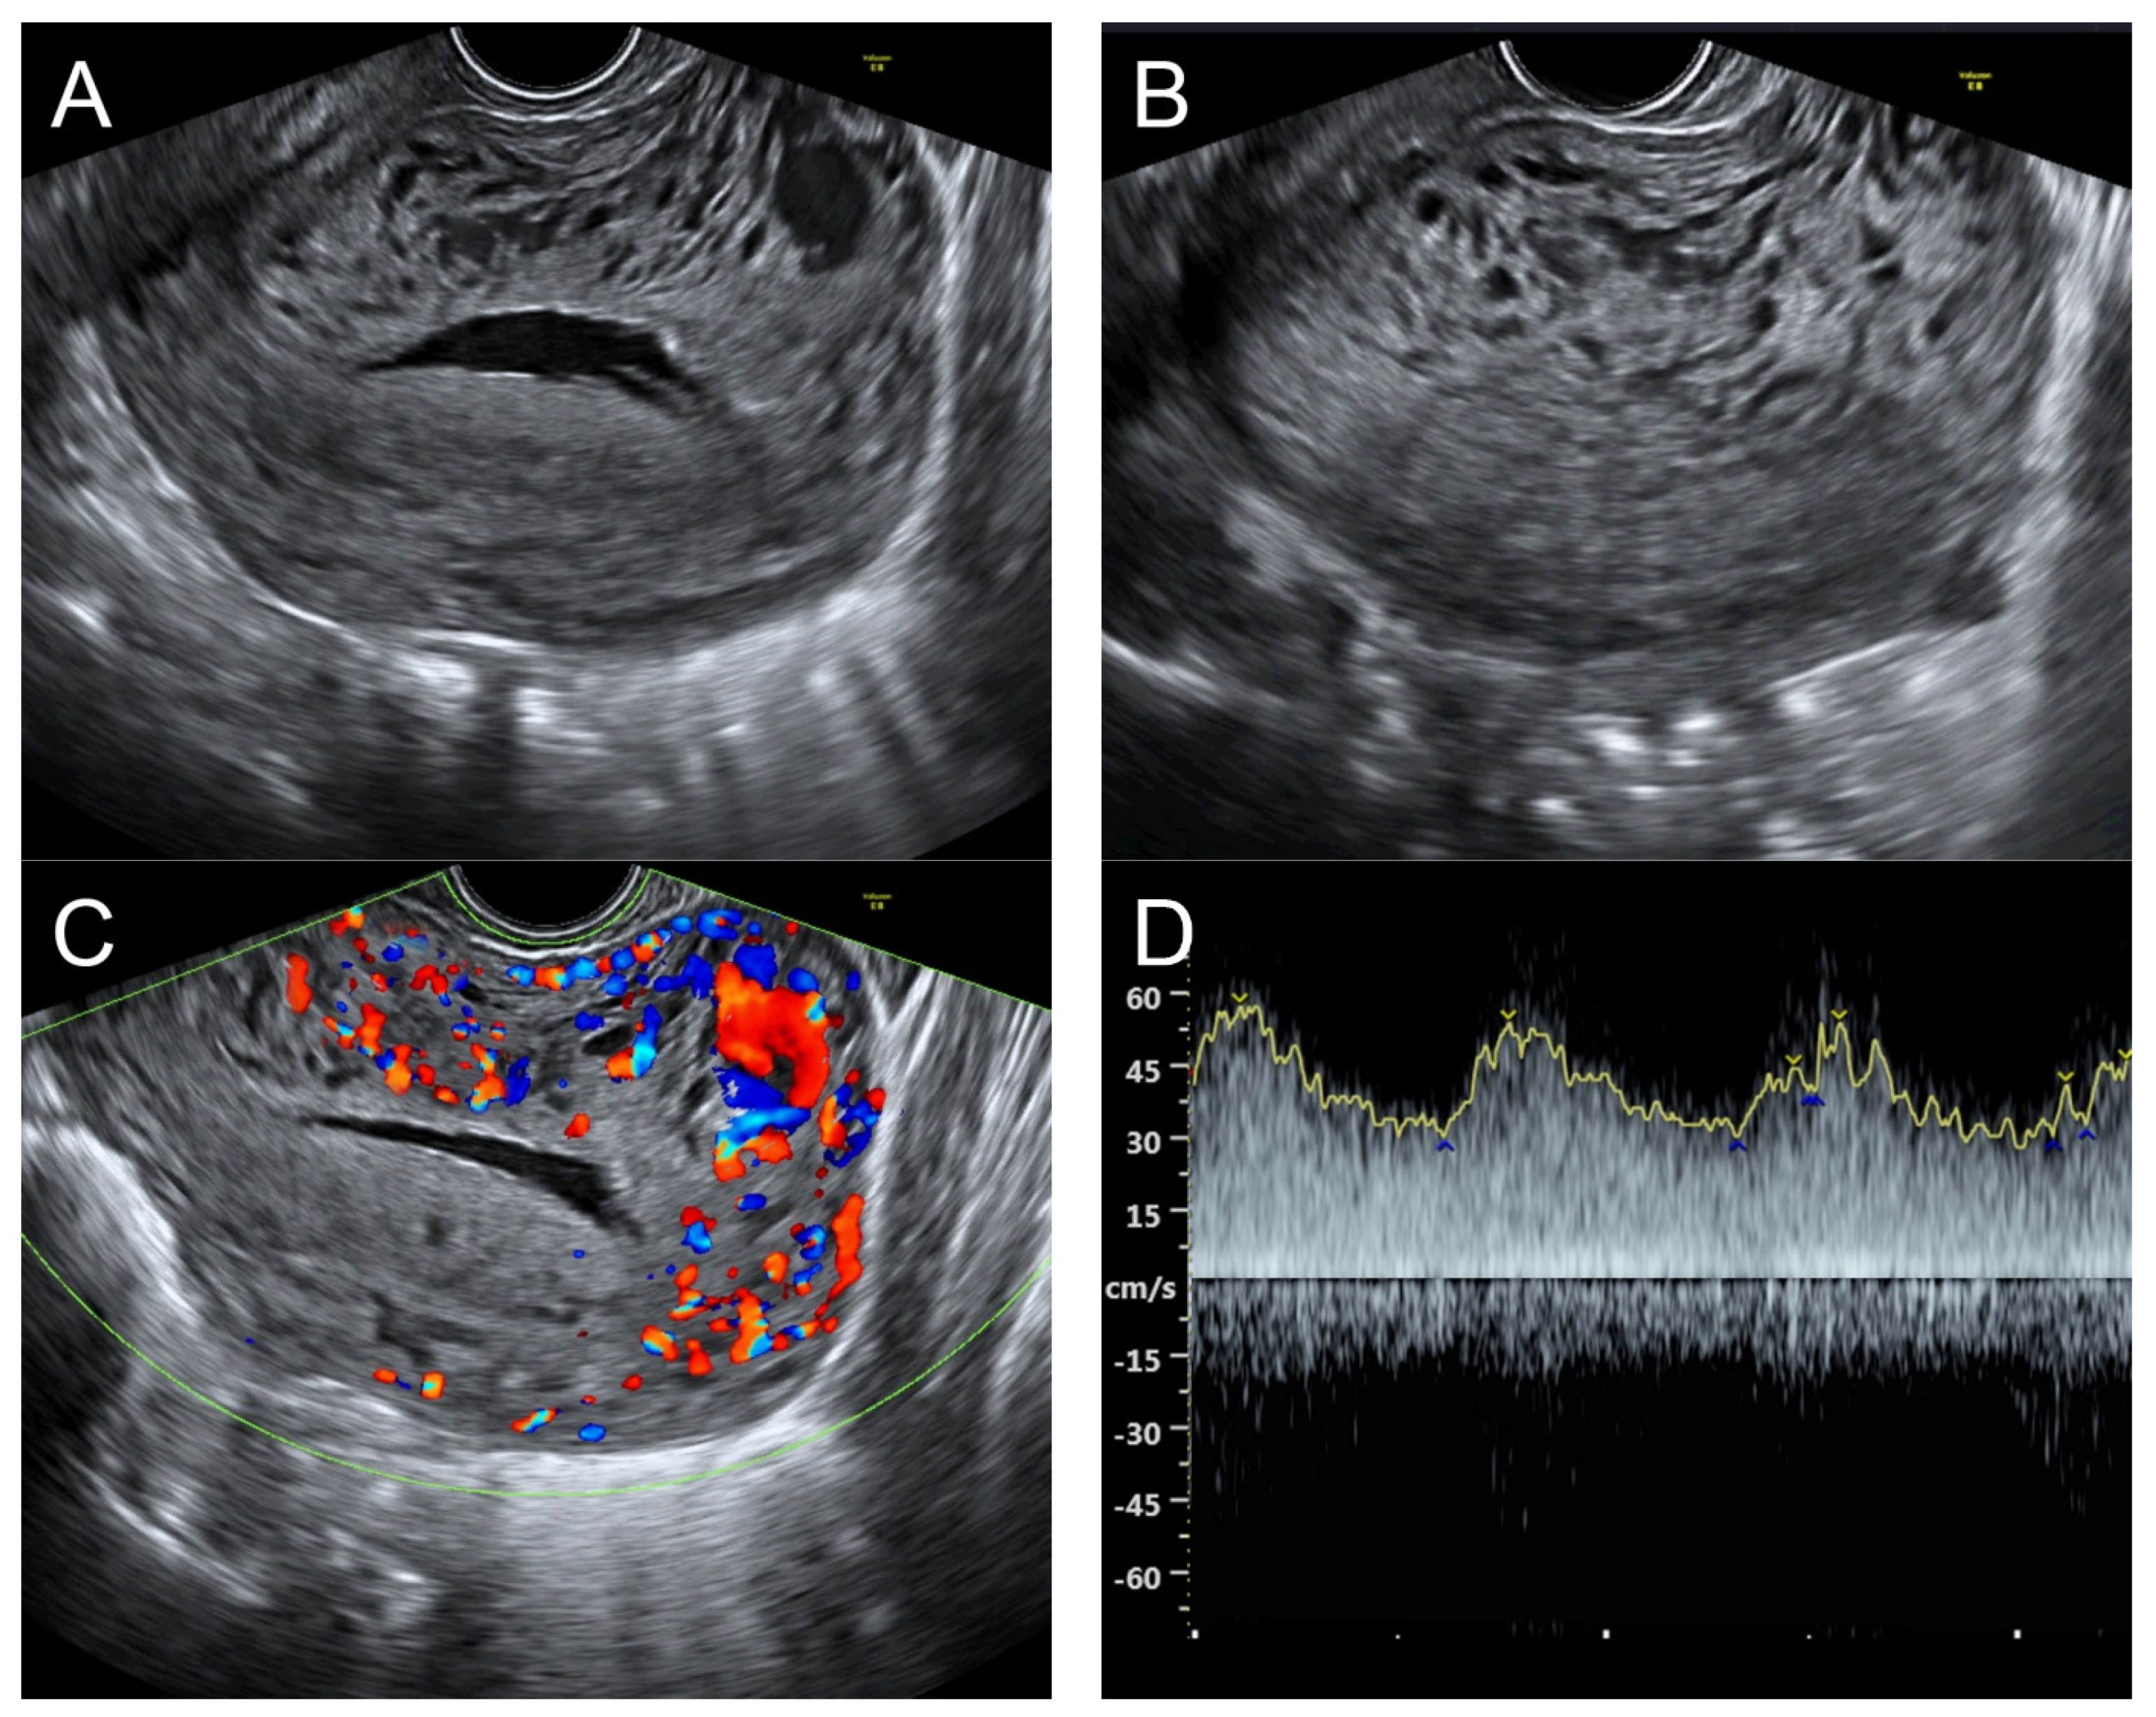

Figure 5. (A,B) Transvaginal ultrasound: sagittal scans of the uterus showed several small anechoic/hypoechoic cysts, giving a spongy pattern and varying in size, throughout the myometrium; no other specific lesions of the uterus. The uterine cavity was lined with a thin endometrium and filled with anechoic fluid, probably lysed blood. (C) Color flow mapping showed hyper-vascularization in the cystic spaces, as seen in figure (A,B), throughout the myometrium and a multidirectional chaotic flow. The main differential diagnosis was adenomyosis or gestational trophoblastic disease. (D) Spectral Doppler showed a high peak systolic velocity (~70 cm/s) with a low resistance index of 0.2.